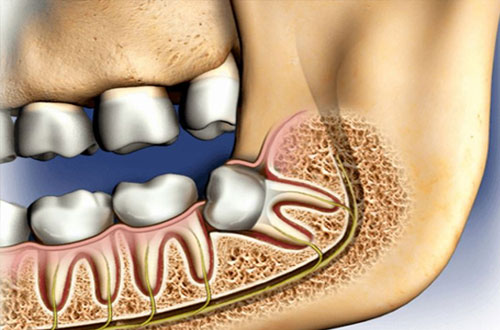

Varför behöver visdomständer opereras?

Ibland kan en operation av visdomstanden krävas och det kan då bero på att omständigheterna kring tanden gör så att den inte går att dra ut. Det kan exempelvis bero på att tanden har vuxit snett, drabbats av en omfattande infektion eller är retinerad, att tanden ligger kvar i käken täck av slemhinna och ibland även ben. Tandens rötter kan även vara böjda vilket gör att det är svårt att dra ut den. I de fall man måste ta bort en visdomstand som sitter komplicerat är operation det bästa alternativet.